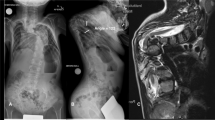

In particular, skull thickness was measured on the axial plane at the standard locations for halo pins: above the eyebrows and lateral to the supraorbital nerves (antero-lateral [AL], right and left) and posterior to the ear above the level of the auditory meatus (postero-lateral [PL], right, and left) using bone windows with the same cut width [21, 22]. All the measurements were obtained using the same CT scan, and bone width cut. The plane of acquisition was adapted to the plane of the halo placement in order to accurately measure the skull width at the site of pin placement. Moreover, skull bone thickness was assessed at four additional sites (i.e., anterior [A], right lateral [Lr], left lateral [Ll], and posterior [P]) using the same axial plane (Fig. 1). A single, senior orthopedic surgeon with expertise in cervical spine surgery (JY) performed all measurements.

Skull bone thickness increased with age for all parameters. In particular, A, AL, PL, L, P skull bone thickness was gradually increased with age, demonstrating good to excellent correlation with age (R = 0.718, R = 0.742, R = 0.836, R = 0.569, and R = 0.6, respectively; P < 0.001). From birth to skeletal maturity, L thickness was increased significantly less (only 58%) compared with AL (205%), P (233%), PL (247%), and A (269%) thickness (P < 0.01). At the end of growth, the thickest point of the vault (absolute value) was found at the P site and the thinnest points were found and both L measurement sites (P < 0.01) (Fig. 2).

Growth of the vault showed a nonlinear progression. Two periods of accelerated growth could be identified. The first period occurred during the first 2 years of life, with AL and PL thickness increasing by 50%. The second period occurred between the age of 10 and 15 years, with AL and PL thickness increasing by 42% (Fig. 2).